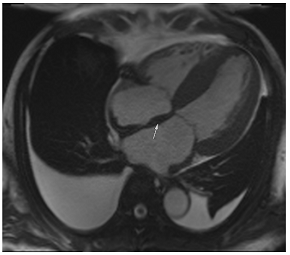

The differential diagnosis of HHD includes hypertrophic cardiomyopathy and its phenocopies (e.g., Fabry’s disease, mitochondrial disease); valvular heart disease (sub-valvular, valvular, and supra-valvular aortic stenosis); pseudohypertrophy (amyloidosis (Table 4A); sarcoidosis (Table 4B)); and the so-called athletic heart, among others. Imaging can plan an important role in elucidating the cause of LVH [47], especially in patients with dual-presence arterial hypertension/HHD and another cardiomyopathy associated with LV hypertrophy.

Example images of various differential diagnoses of hypertensive heart disease.

Cardiovascular magnetic resonance (CMR) uniquely allows tissue characterisation to be undertaken and as such, can readily differentiate hypertensive LVH from causes of pseudohypertrophy or thickening of the left ventricle due to myocardial infiltration with amyloid (Table 4A) or sarcoid (Table 4B) [47].

12. Cardiac Amyloid

Cardiac amyloid is typically characterised by the thickening of the ventricular walls, atria, and valvular structures (Table 4A). There is usually reduced long-axis motion. Native T1 and extracellular volume (ECV) are increased, and the latter may potentially be used as a marker of the degree of infiltration, and to monitor response to therapy. The findings on late gadolinium enhancement imaging are characteristic of abnormal gadolinium kinetics (the myocardium nulling in advance of the blood pool), difficulty in achieving a suitable null time, and widespread circumferential subendocardial enhancement [49]. When the latter involves the LV sub-endocardium and the RV aspect of the septum, it can give rise to the so-called zebra-stripe sign (Table 4C) [49]. The LV thickening seen in amyloid is often described as concentric, but asymmetrical patterns of thickening not too dissimilar to the patterns seen in hypertrophic cardiomyopathy are not infrequently encountered, and so the pattern of thickening alone cannot be used for differential diagnosis [50]. CMR findings are often accompanied by signs of fluid overload in the form of pleural or pericardial effusions (Table 4A,C), but these may not be seen in early disease. Efforts to differentiate between ATTR and AL using CMR have been made, and comparisons show more extensive LGE, LGE of the RV, and higher LV mass in ATTR versus less extensive more subendocardial LGE in AL [51]. The overlap between AL and ATTR amyloidosis, though, remains substantial. ATTR cardiac amyloid can also be readily identified by 99mDPD bone scintigraphy, particularly in the absence of light chain excess or evidence of a paraprotein or plasma cell dyscrasia [52]. Emerging PET tracers, such as delayed [18F]-florbetapen cardiac uptake, represent promising biomarkers, which may discriminate cardiac amyloid infiltration due to AL from ATTR and in future may further obviate the need for endomyocardial biopsy [53].